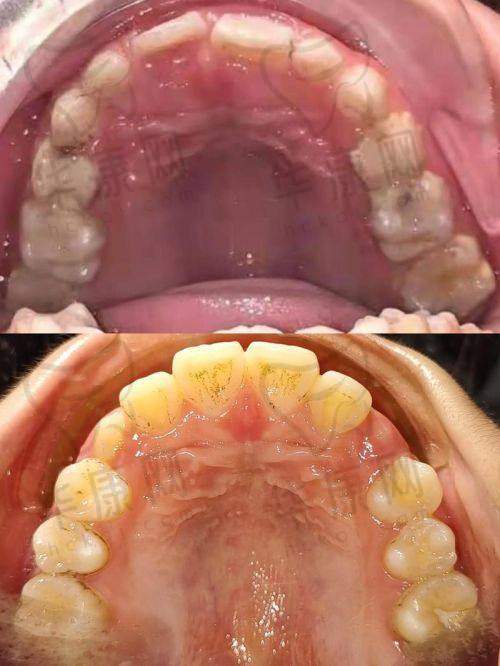

南宁怡友中海口腔青少年早期矫正成功实例

南宁怡友中海口腔在青少年早期矫正方面已经取得了不少成功实例。例如,小明(化名)是一名12岁的男孩,由于牙齿排列不齐,影响了面部美观和自信心。家长带他来到南宁怡友中海口腔,医生为他制定了个性化的矫正方案。经过一年多的矫正治疗,小明的牙齿变得整齐美观,面部轮廓也得到了改善。小明不仅修复了自信,还更加注重口腔卫生和健康。

又如,小红(化名)是一名10岁的女孩,存在地包天的问题。医生通过早期干预和矫正治疗,成功纠正了她的牙齿畸形,避免了后期更复杂的治疗。现在,小红的牙齿和面部发育都非常正常,家长对治疗成效非常满意。